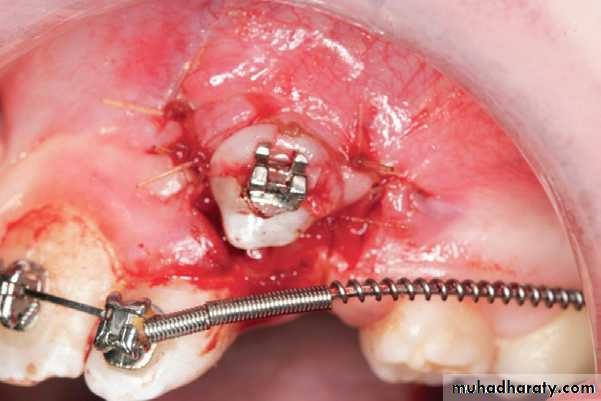

Two basic approaches, either a “closed” or “open” technique, are used to provide access to the impacted canine.In the “closed eruption” Technique, the crown of the canine is exposed, the orthodontic eruption device is attached to the crown, and the flap is sutured back over the tooth, leaving only the eruption chain exposed for orthodontic manipulation. The eruption chain is usually exited through either the crestal incision or the extraction site of the primary canine and ligated to the archwire or brackets on the adjacent teeth.

“closed eruption”technique

Surgical exposure of impacted canine

Flap, closed eruption procedure for exposure (A) and bonding (B) of palatally impacted tooth (C), Flap sutured back over

the tooth, leaving only the eruption chain exposed.

The treatment options for the palatally impacted canine include open or closed eruption techniques.After removal of the deciduous teeth, a palatal flap is created, underneath which part of the bone covering the teeth is exposed. A round bur is then used to remove the bone covering the crowns and orthodontic brackets are placed for traction of the teeth into their normal position in the dental arch. The area is then irrigated with saline solution and the flap is closed with interrupted sutures.